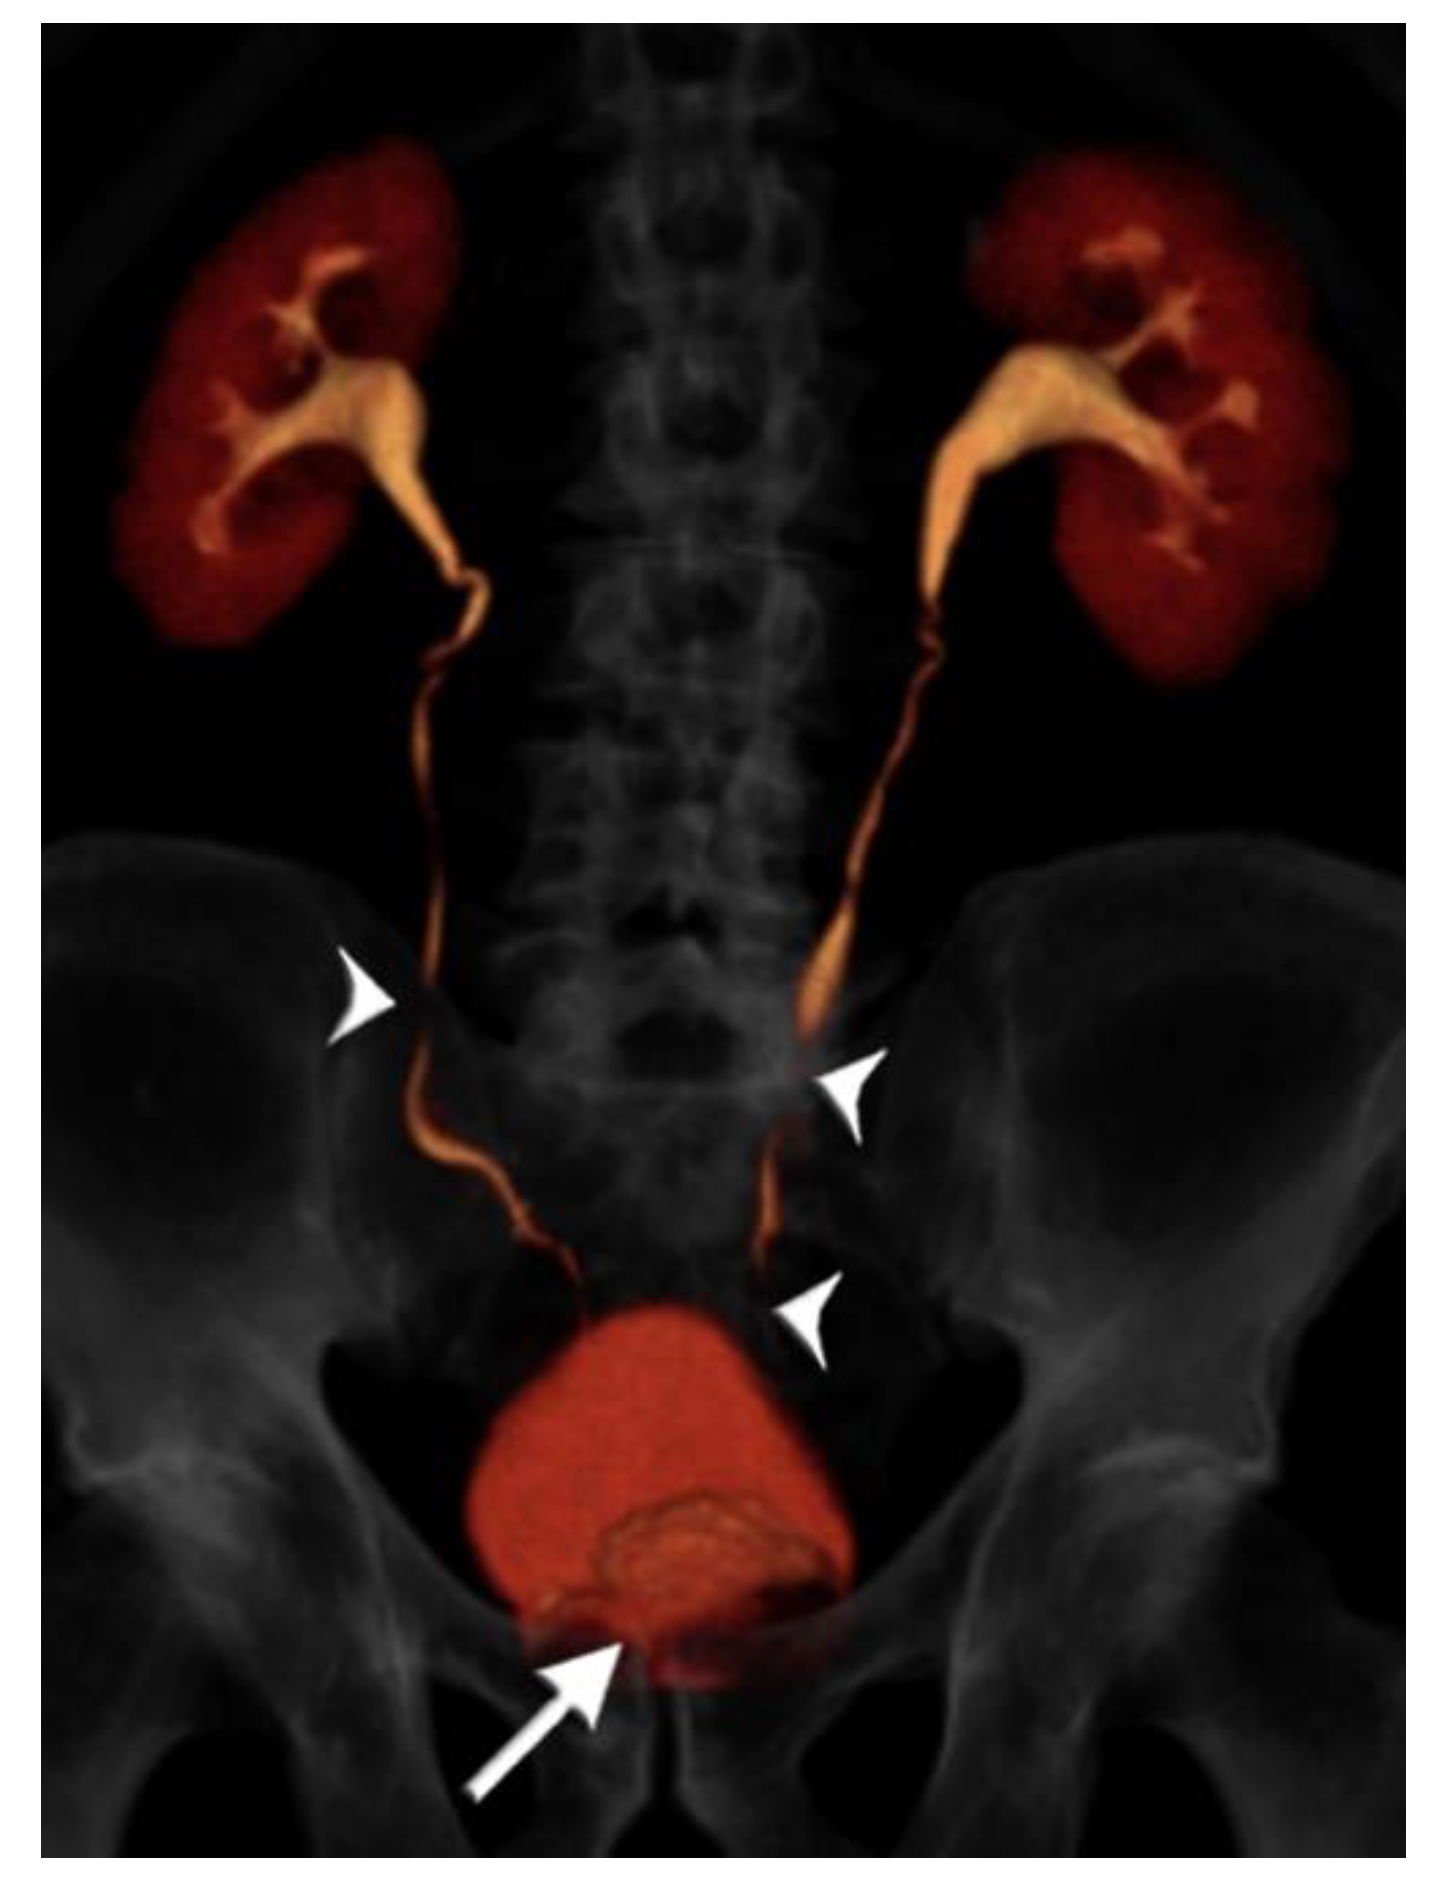

2.2. CT Urography Technique

- Noorbakhsh, A.; Aganovic, L.; Vahdat, N.; Fazeli, S.; Chung, R.; Cassidy, F. What a difference a delay makes! CT urogram: A pictorial essay. Abdom. Radiol. 2019, 44, 3919–3934. [Google Scholar] [CrossRef]

- Cheng, K.; Cassidy, F.; Aganovic, L.; Taddonio, M.; Vahdat, N. CT urography: How to optimize the technique. Abdom. Radiol. 2019, 44, 3786–3799. [Google Scholar] [CrossRef]